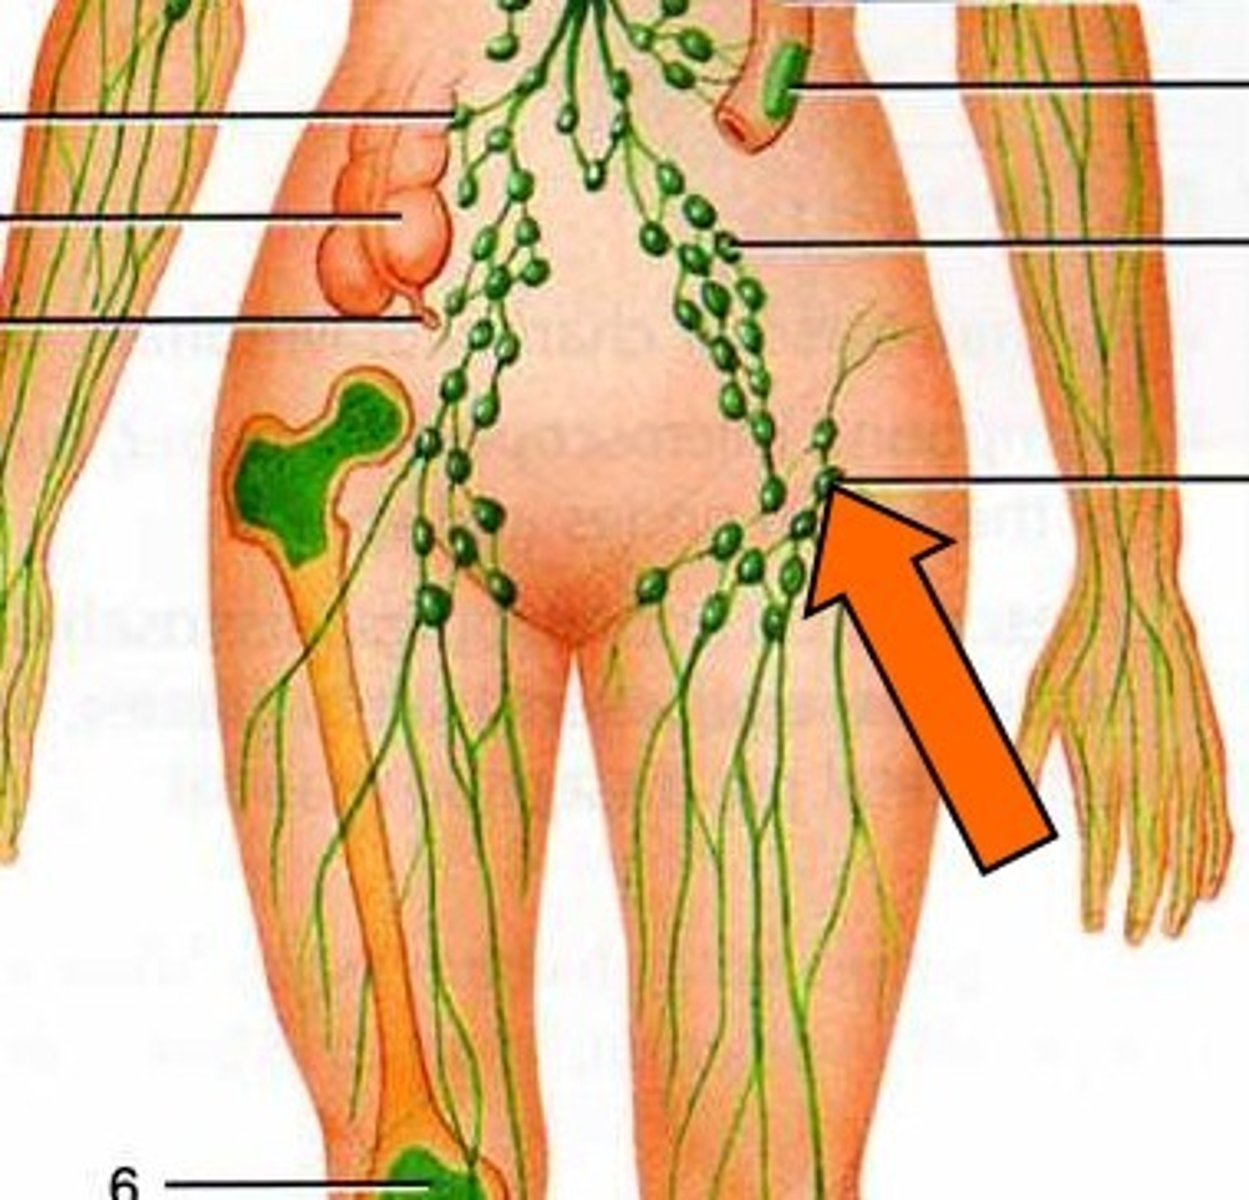

Secondary lymphoid tissues

Lymph nodes, spleen, and mucosa-associated lymphoid tissue (MALT)

What do the lymph nodes do?

Filter lymph --> trap pathogens for destruction by white blood cells

S+S: Painless enlargement of lymph nodes in neck, axilla, or groin, fever, weight loss